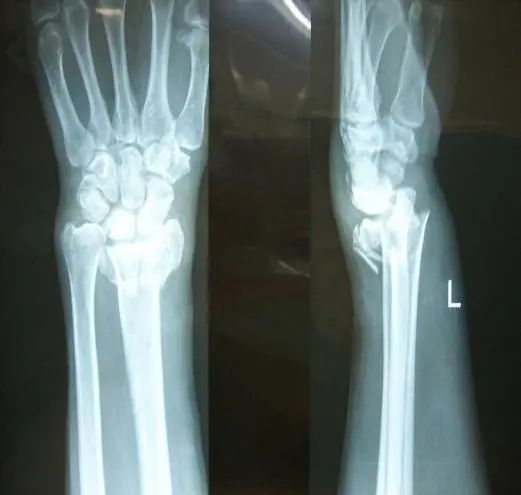

駝背、變矮、腰腿痛

您是否經(jīng)歷過骨折的痛楚?

手術(shù)、住院、難以動彈

X線攝片只有在骨量減少達(dá)到30%以上后,才能通過X射線檢查出來,對于早期骨質(zhì)疏松癥狀很難發(fā)現(xiàn)。而該儀器對于診斷骨質(zhì)疏松、評估骨折風(fēng)險及骨質(zhì)疏松治療效果能得到精確評價。